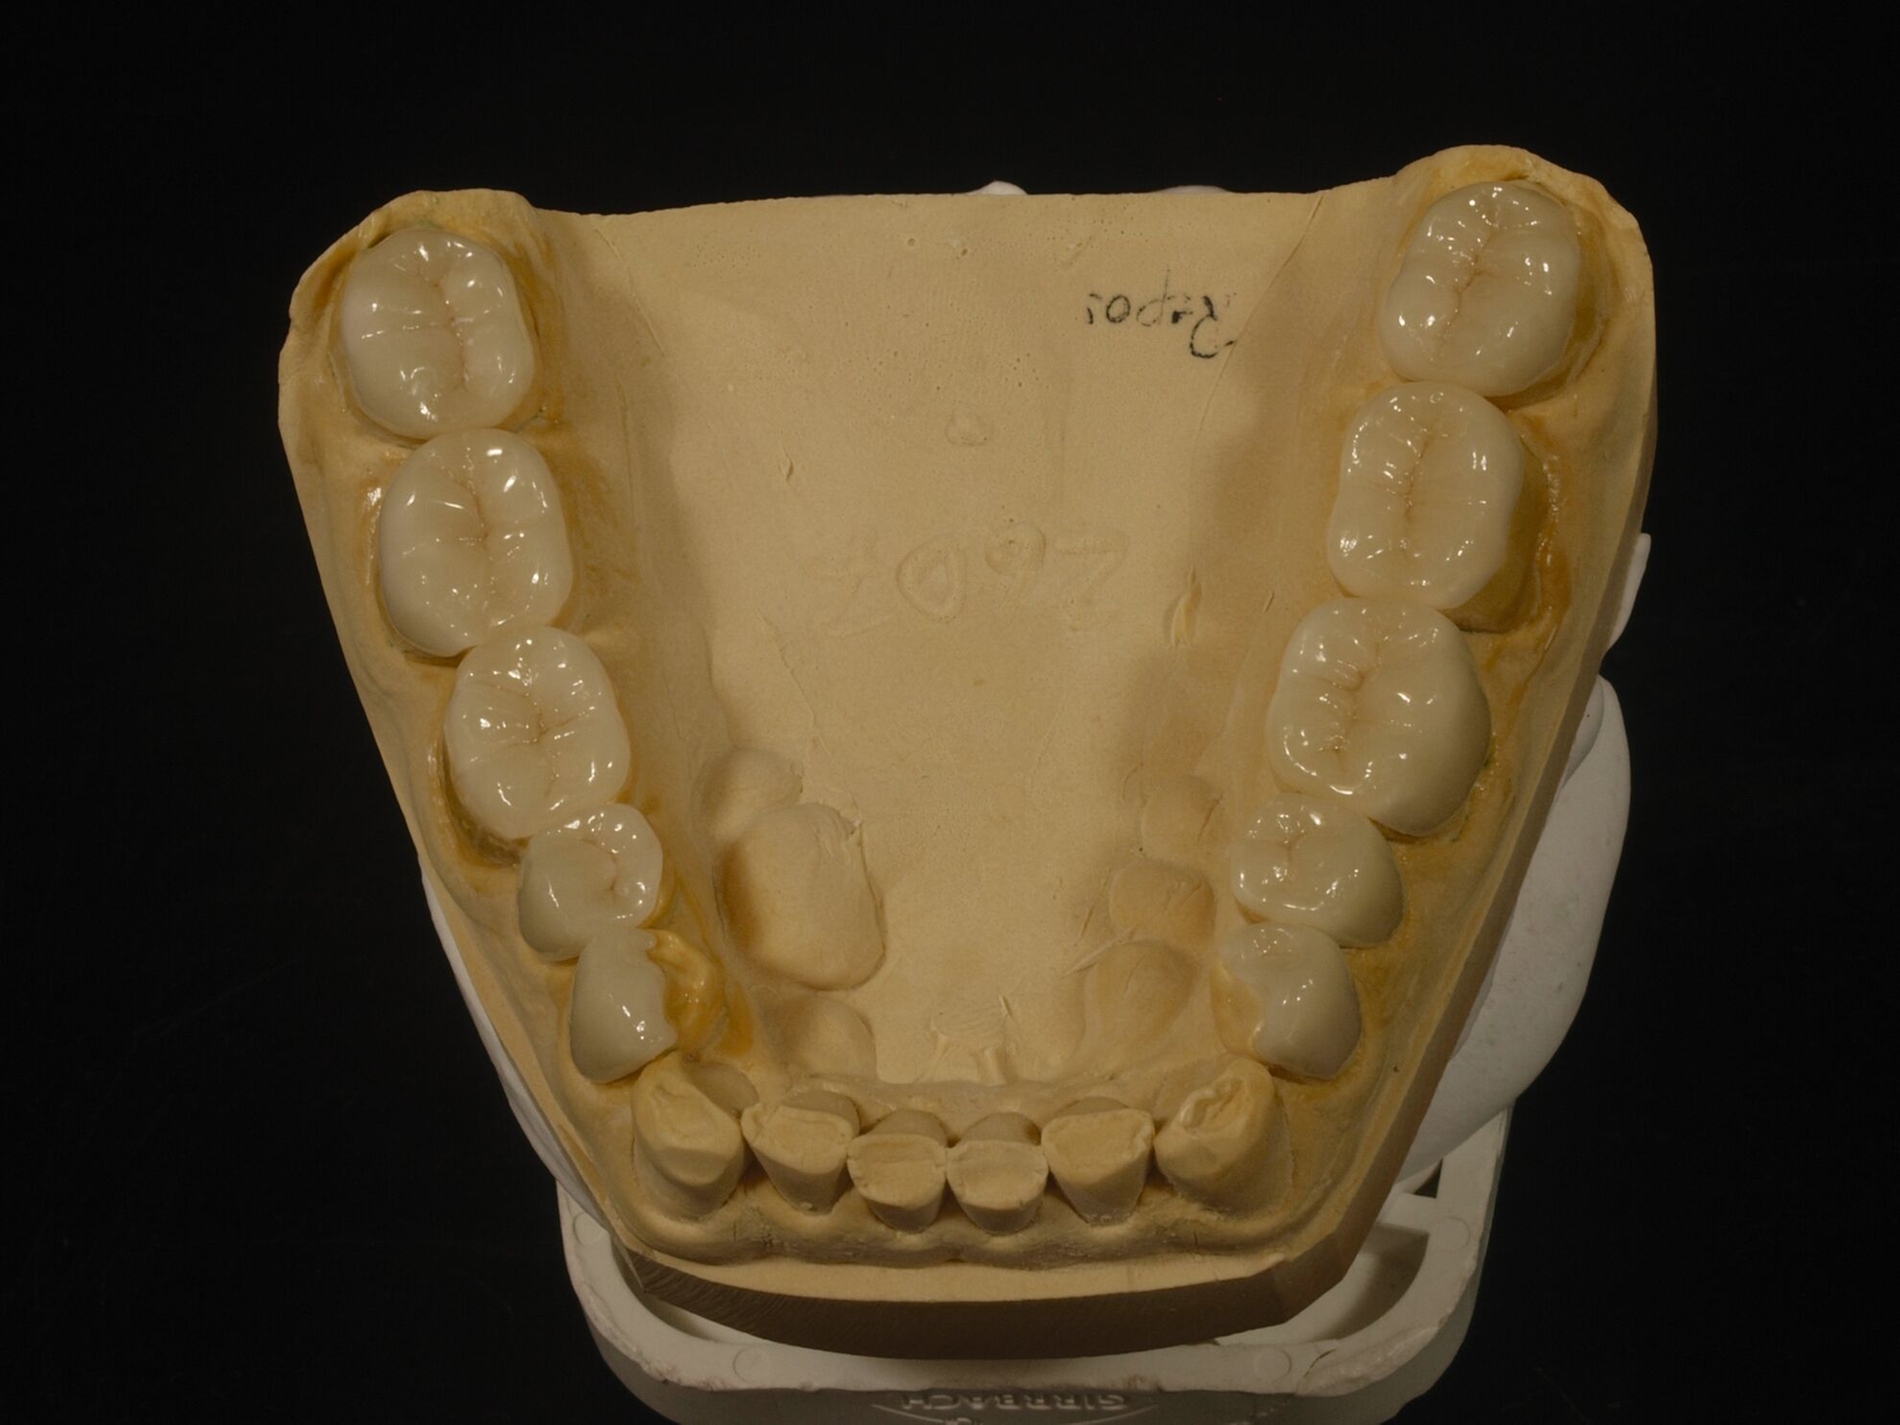

Auch erheblicher Zahnverschleiß lässt sich theoretisch mittels intraoral direkt verarbeiteter Komposit-Restaurationen behandeln. Dies erfordert dann allerdings zusätzlichen erheblichen zahntechnischen Vorbereitungsaufwand. An dessen Anfang stehen indirekte Präzisionsabformungen, die darauf beruhende Herstellung von Kiefermodellen und Duplikaten aus Superhartgips, deren schädelbezügliche Montage im Artikulator wegen der nachfolgenden Änderung der vertikalen Dimension.

Die Position des Unterkiefermodells wird zumeist auf der Grundlage von Registraten festgelegt. Die AWMF-Leitlinie zur instrumentellen Funktionsanalyse der DGFDT [Utz et al., 2022] empfiehlt, bei funktionsgesunden Patienten, die bei natürlicher Bezahnung in maximaler Interkuspidation gut abgestützt sind, diese Unterkieferposition in der Regel zu übernehmen (Empfehlung 25). Anders ist es, wenn zu wenige interokklusal abstützende Zähne vorhanden sind, eine sekundäre Unterkieferverlagerung vorliegt – etwa durch Zahnverschleiß – oder der Kauflächenkomplex insgesamt restauriert werden muss; in diesen Fällen sollte die vorliegende habituelle Okklusion in die restaurative Behandlung nicht übernommen werden. „In diesen Fällen hat sich die zentrische Kondylenposition, die dann zur zentrischen Okklusion wird, als Referenzlage bewährt (Empfehlung 26).“

Diese Simulation der Okklusion bildet die Voraussetzung für das nachfolgende Wax-Up der geplanten Zahnform als zahntechnische Planungsgrundlage. Das so ergänzte Kiefermodell wird anschließend dubliert, als Grundlage der Herstellung neuer Kiefermodelle in neuer Kontur, auf denen wiederum speziell verstärkte Formteile für die spätere intraorale Ausformung der Komposite erstellt werden. Die Ausformung der Restaurationen aus Kompositen und ihre Aushärtung erfolgen insofern zwar intraoral „direkt“, das Gesamtvorgehen ist aber an die gleichen zahntechnischen Vorarbeiten gebunden wie eine Therapie mittels indirekter Restaurationen. Solchermaßen hergestellte Restaurationen überstehen nach Untersuchungen der engagierten Kollegen aus Zürich drei Jahre in gutem Zustand [Schmidlin et al., 2009]; nach fünf Jahren ist der Zustand allerdings beeinträchtigt [Attin et al., 2012].

Für die Behandlungsabfolge bestehen verschiedene Möglichkeiten, die unmittelbar mit der Kontrolle der Gelenkstellung verbunden sind. Generalisierter Zahnverschleiß erfordert häufig eine Behandlung aller Zähne zumindest eines Kiefers, weil der vertikale Platzbedarf zum Schutz der geschädigten Zähne eine Erhöhung der vertikalen Dimension erfordert. Dies bedingt insofern eine zeitgleiche Versorgung aller behandelten Zähne zumindest im Seitenzahnbereich, weil sonst eine ungleichmäßige Abstützung resultiert. Bewährt hat sich die Aufteilung derartig aufwendiger Behandlungen in mehrere Abschnitte. Dabei erfolgt im ersten Abschnitt die Abstützung im Seitenzahnbereich in neuer VD, in der Regel einhergehend mit einer semipermanenten Versorgung der Frontzähne zur Wiederherstellung der dynamischen Führung in neuer VD. Im begründeten Ausnahmefall kann dieser Schritt entfallen, etwa bei unmittelbar nachfolgend geplanter Behandlung der Frontzähne; in dem Fall erfolgt die Steuerung der dynamischen Okklusion in der Zwischenzeit mit einer entsprechend gestalteten Okklusionsschiene, die auch tagsüber getragen wird (Abbildung 11).